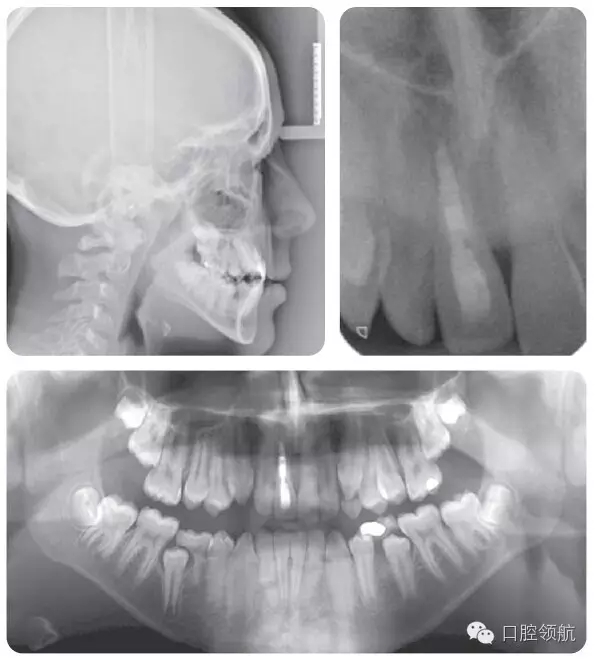

牙根外吸收可以通過牙齒的松動度來判斷。在一些病例可能發(fā)生根骨粘連,并且牙齒位置較鄰牙常表現(xiàn)為未能萌出至平面。叩診該患牙呈高調(diào)、濁音。正畸力往往難以使該牙產(chǎn)生移動。臨床和X線片檢查(圖2.47)顯示該患者的UR1發(fā)生了根骨粘連。